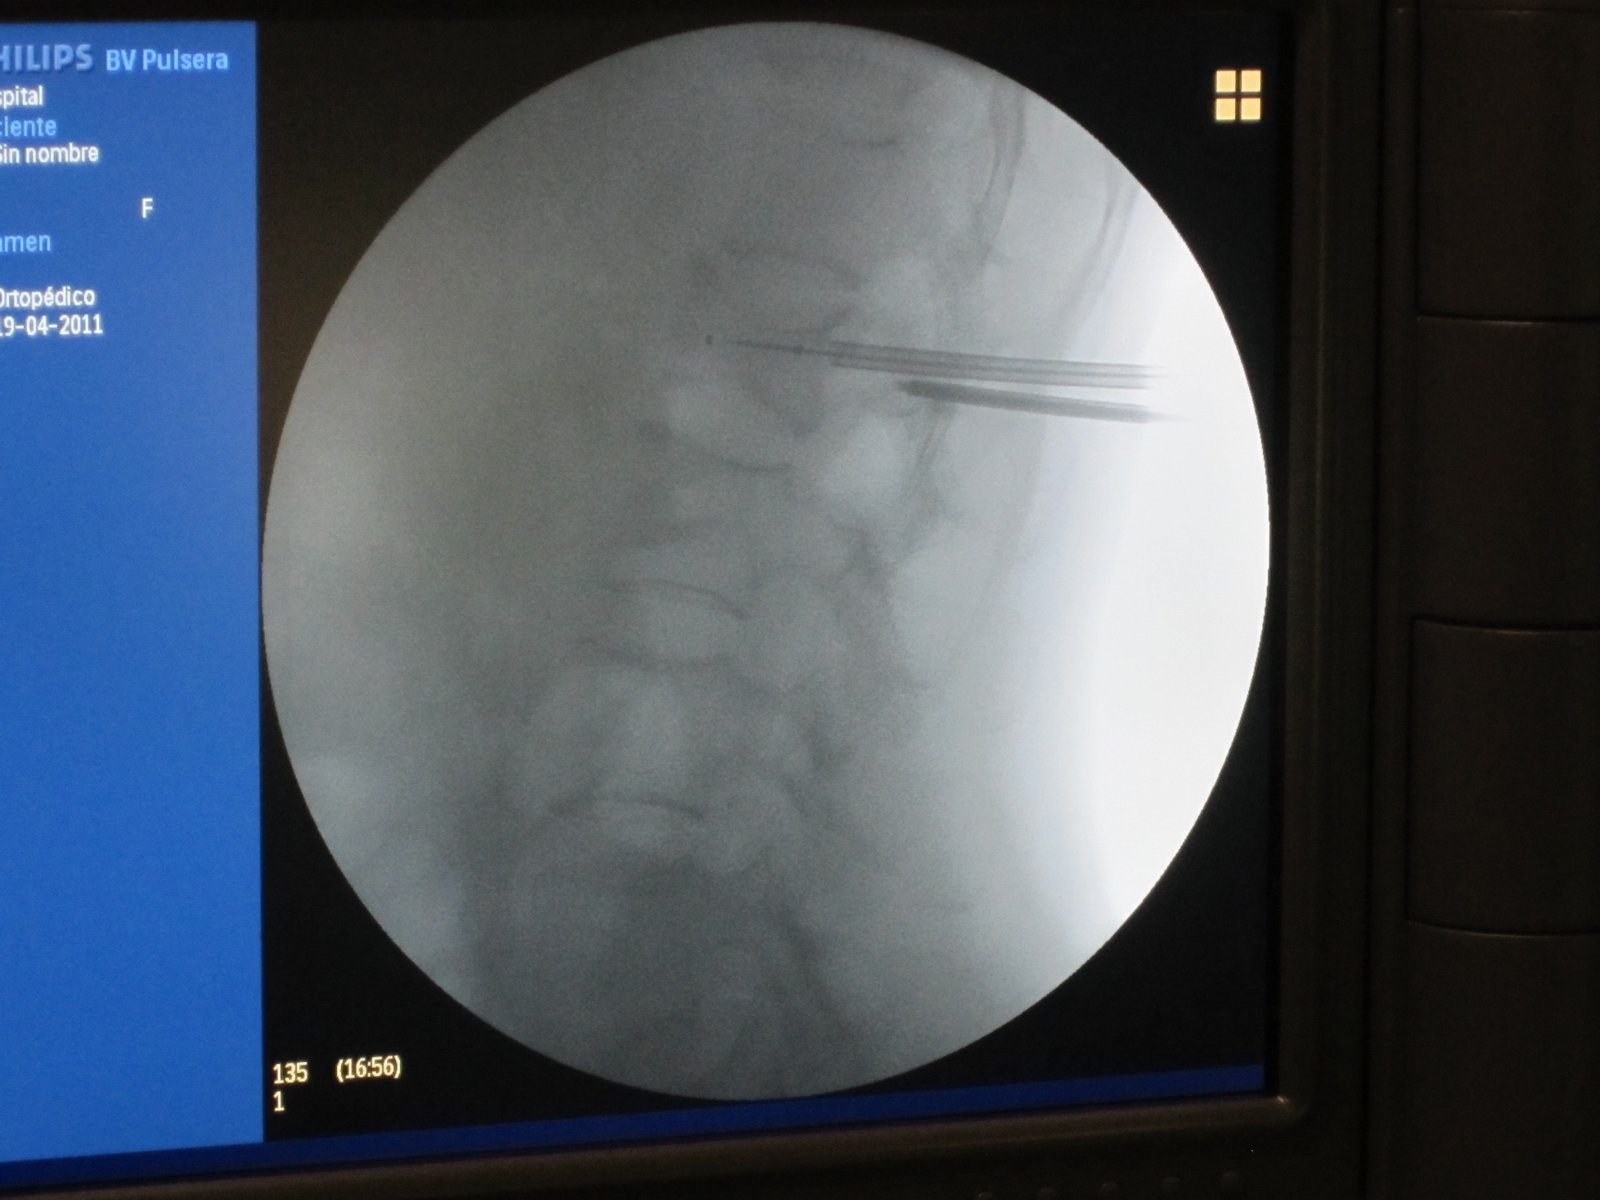

Estimulador de Cordones (SCS)

Tecnología que calma el dolor de forma automática, sin necesidad de cirugía mayor.